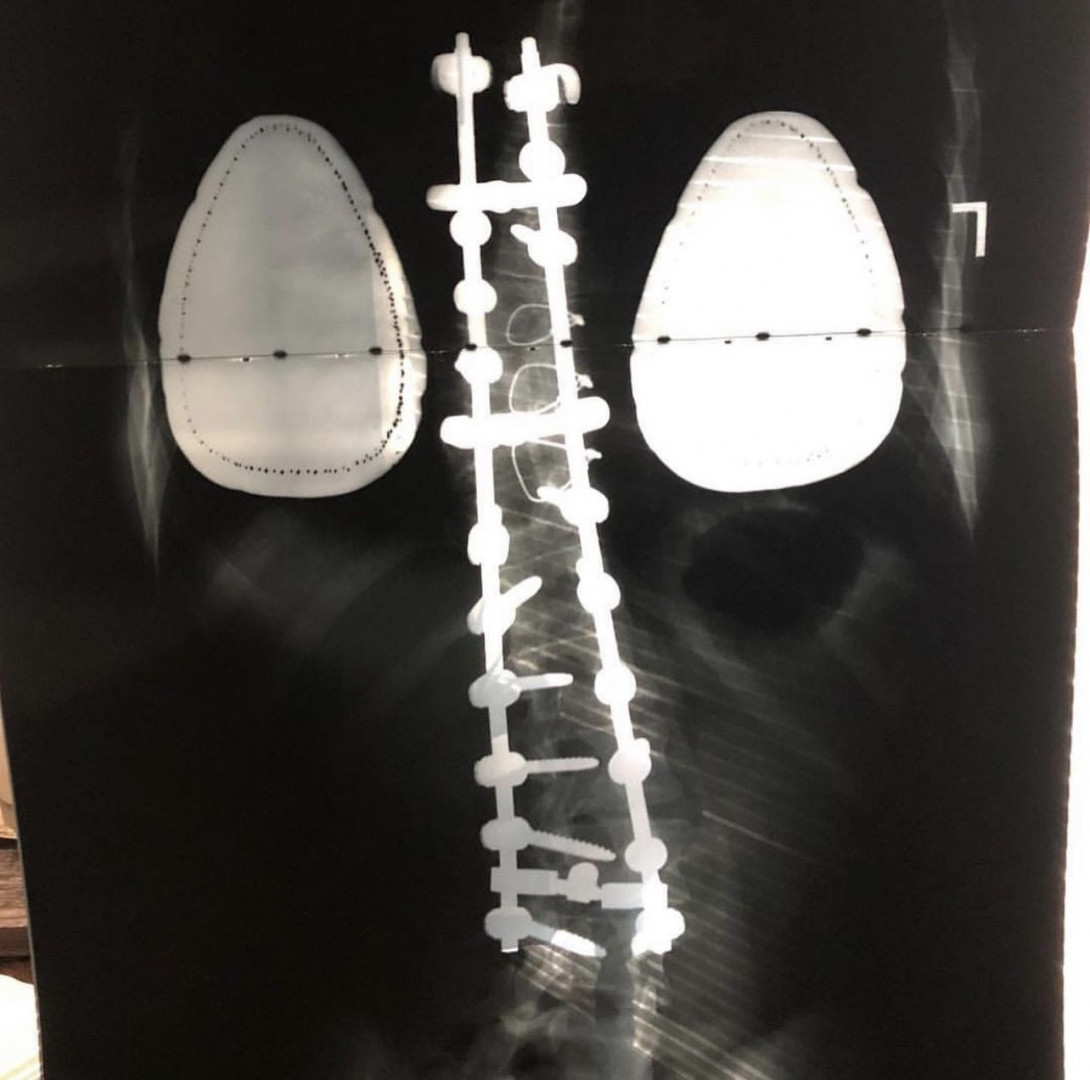

My favorite way to train is by integrating mobility, strength training, and functional fitness to support long-term health and performance. With a fused spine, mobility is essential for recovery, injury prevention, and movement quality. Strength and functional training build resilience, efficiency, and confidence—allowing me to lead by example and show that sustainable fitness is achievable for every body.